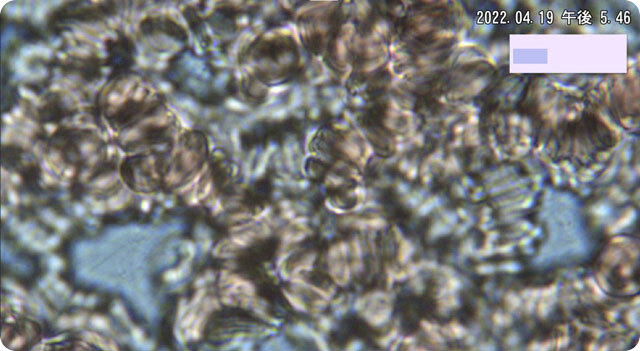

以下に血液の動画観察で確認される状態の一例(参考画像)

血液を顕微鏡で観察すると、赤血球や白血球とは別に、とても小さな粒子のような動きが見られることがあります。

これらは、血液観察の分野では「ソマチッド」と呼ばれていますが、医学的に正式な血液成分として認められているものではありません。

当院では、指先からほんの1滴だけ血液を採り、そのまま顕微鏡で観察する「生きた血液の動画分析」を行っています。

採取した瞬間そのままの血液を映し出すため、赤血球や白血球の動き・形・状態など、身体の “ 今の様子 ” をより、リアルに確認することができます。